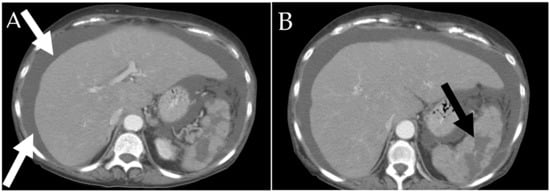

6.2.2. Liver and Spleen